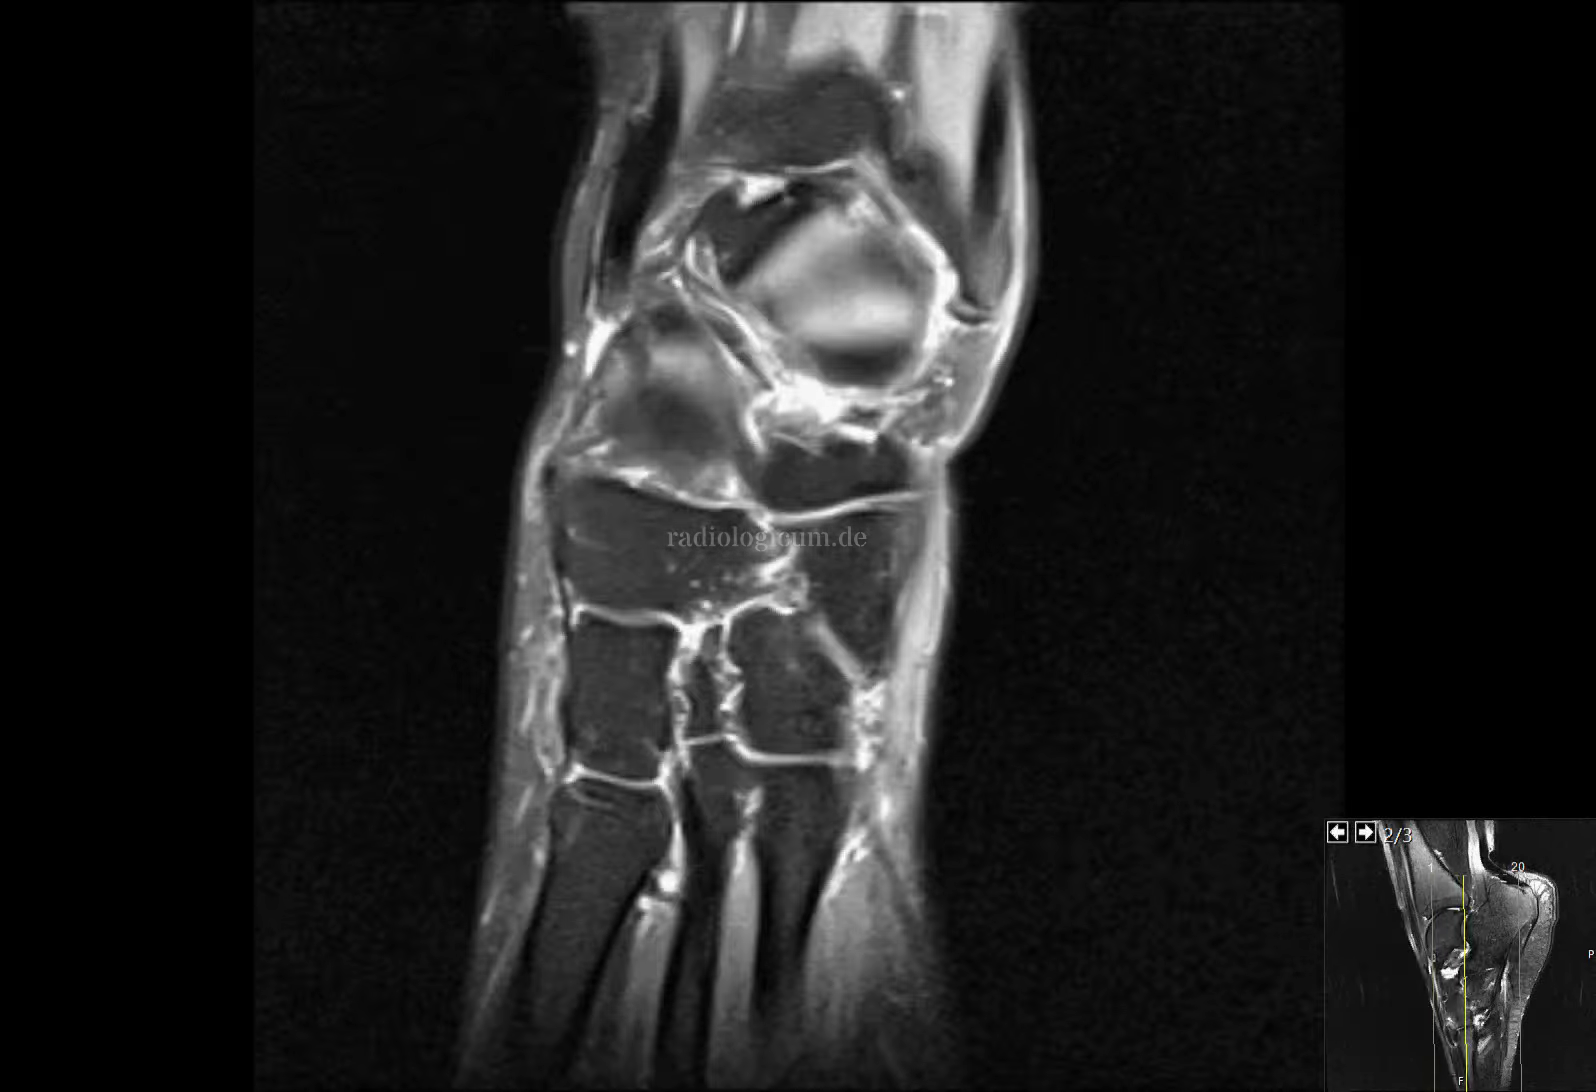

Os naviculare secundarium - Syndrom December 21, 2020Muskuloskelett apRtg sagPDfs traPDspair Headings Dieser Fall wurde noch nicht annotiert.